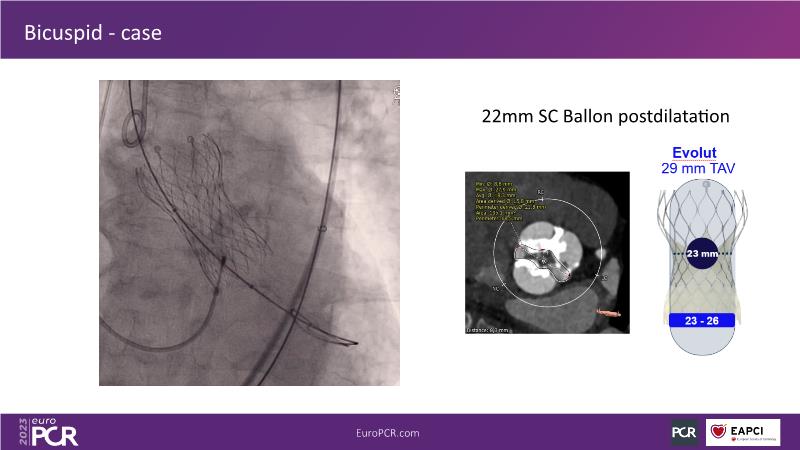

Discover the key factors to consider in selecting the optimal valve and implant technique for transcatheter aortic valve implantation (TAVI) to achieve optimal procedural outcomes. Gain insights into the impact of device choice and implantation technique on coronary access following TAVI and learn valuable strategies for tailoring your TAVI technique to complex scenarios, including bicuspid aortic valves, large and calcified anatomies, and ensuring coronary access.

- To learn how to tailor your TAVI technique to complex situations: bicuspid aortic valves, large, calcified anatomies and coronary access